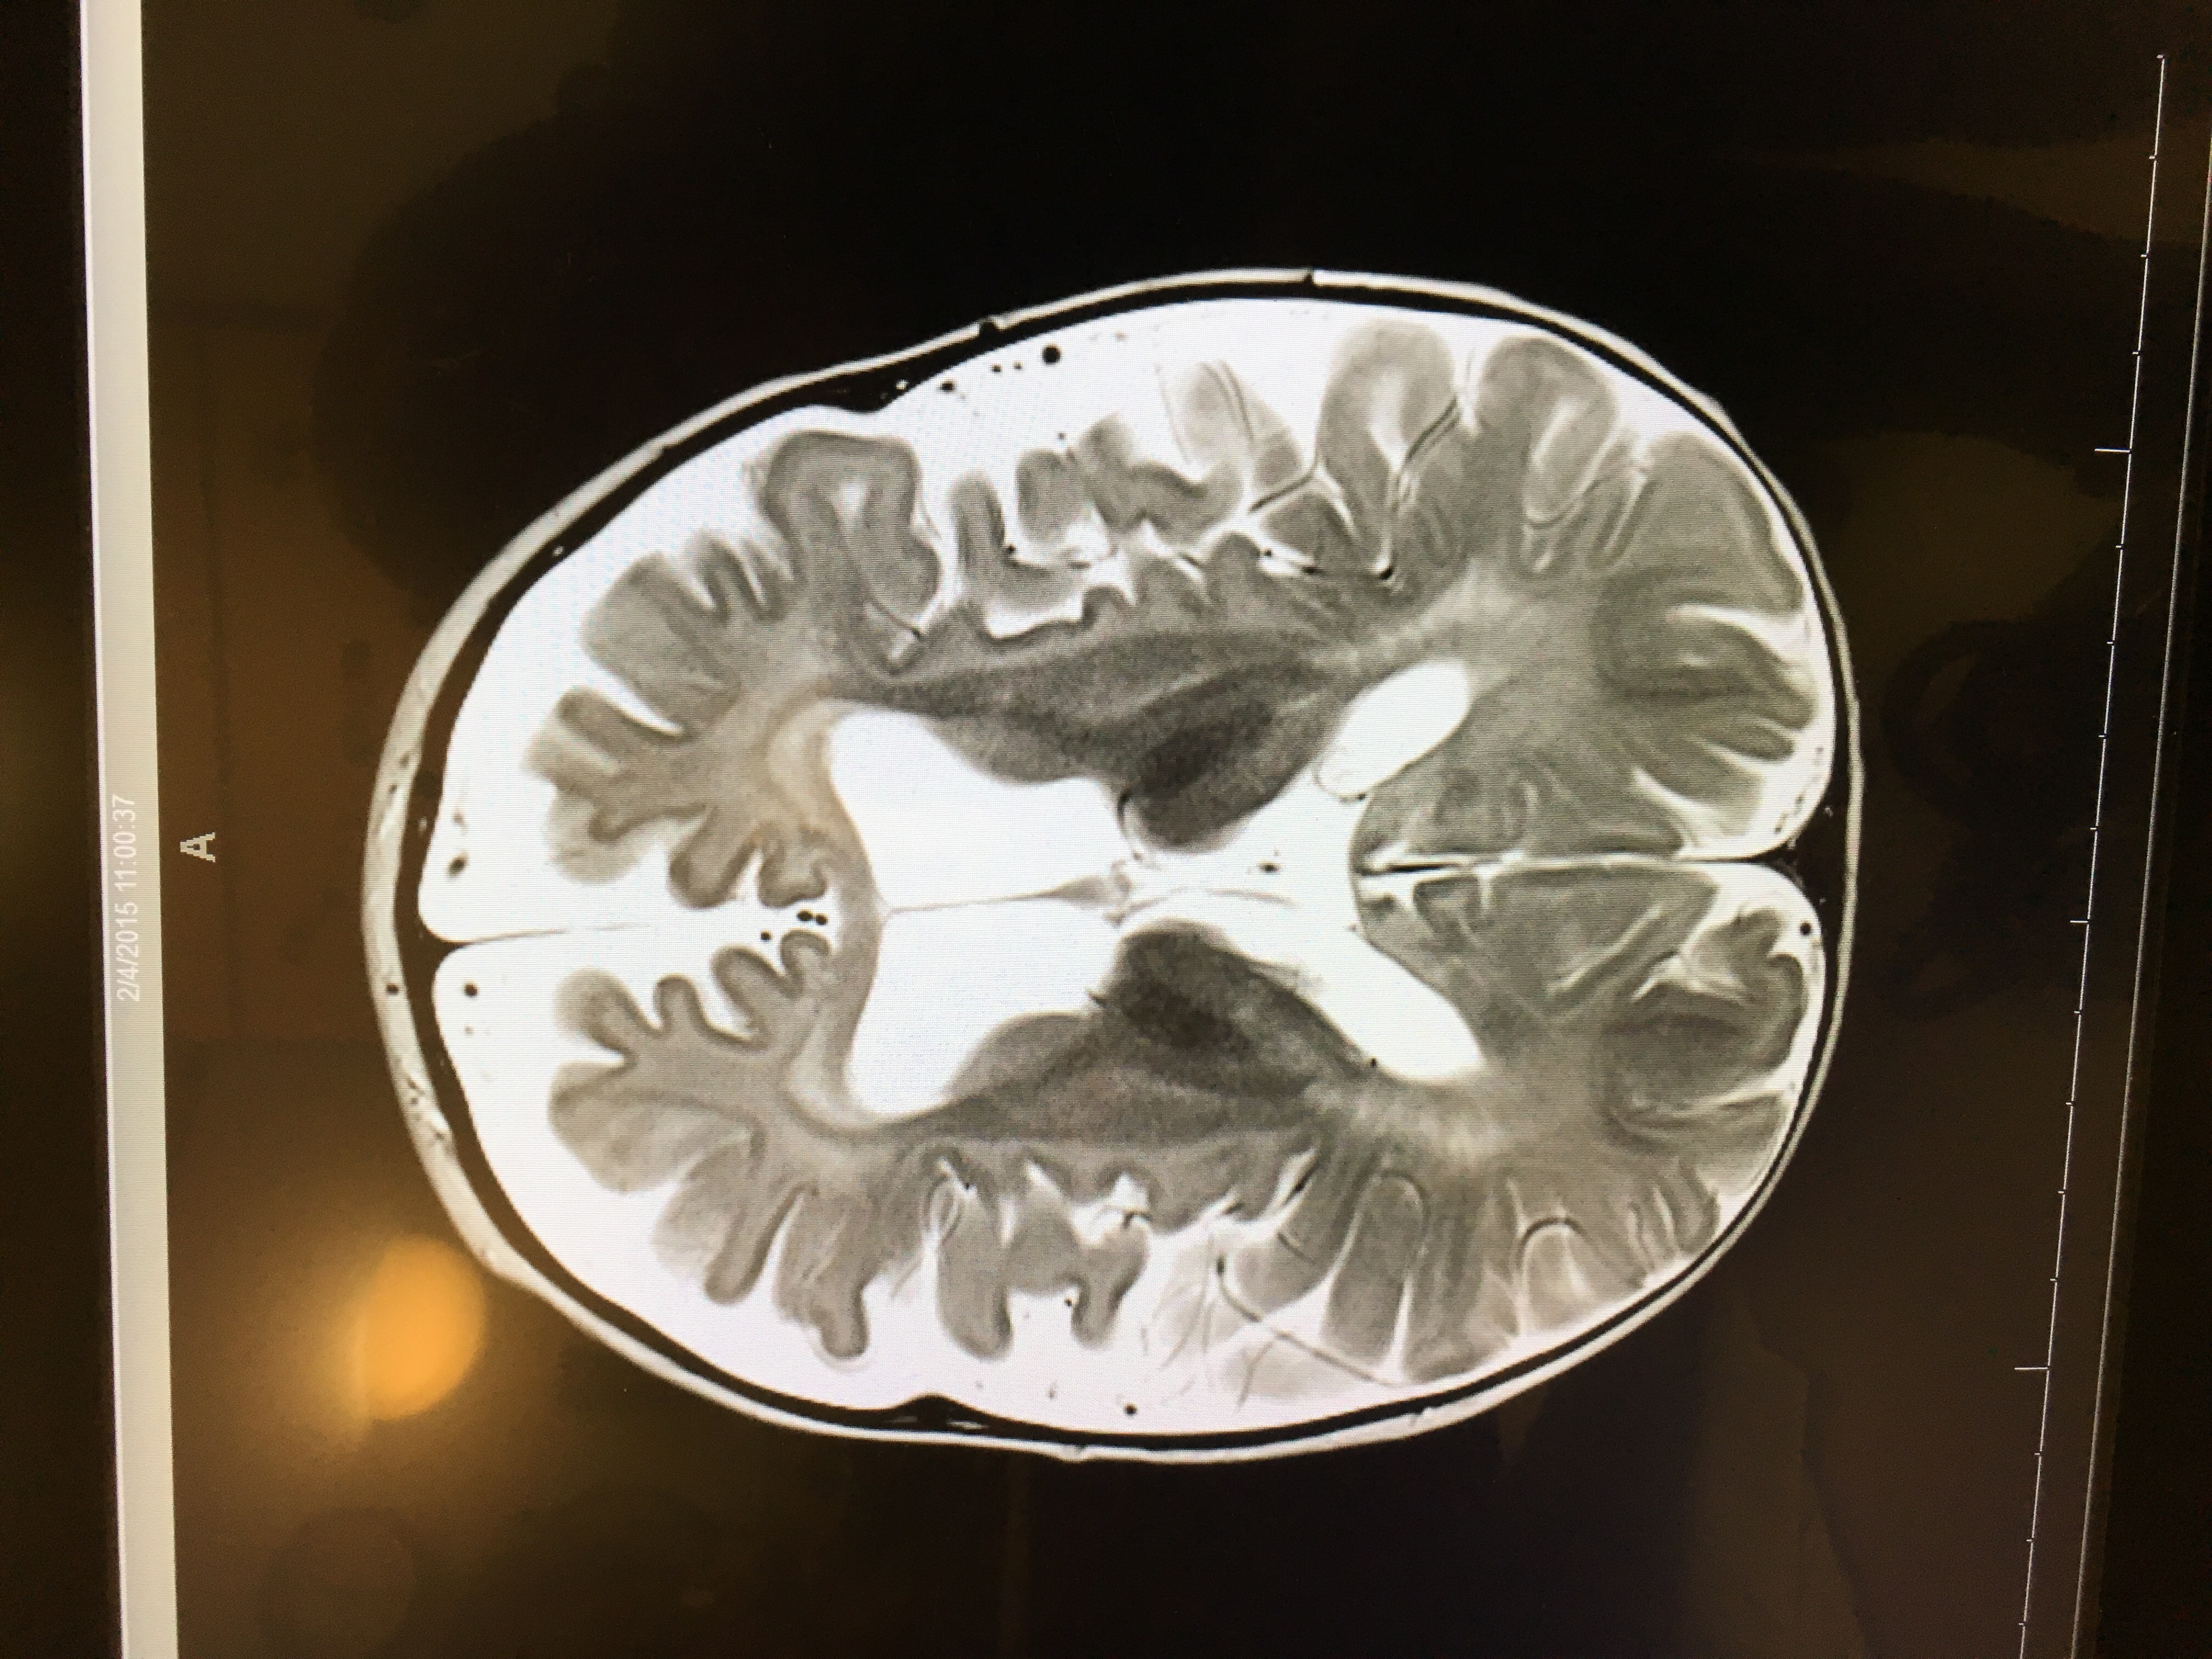

We didn’t see the images of the MRI (or learn in detail about what they saw) until February 6th, but I want to include them in this post.

We have never shared these publicly.

Here are two screenshots of Tori’s brain on February 4, 2015.

We knew then that something was seriously wrong, even from our medically-untrained perspective.

Tori will have another MRI later this month and I will be very interested to compare the images to see the disease progression.

Krabbe is a terrible, horrible disease and every child should have the opportunity to be screened for it (and other leukodystrophies) at birth. 💙